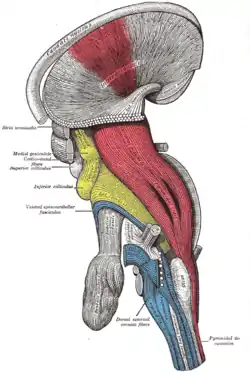

Coronal section of brain through anterior commissure. Superficial dissection of brain-stem. Lateral view. The caudate nucleus can be seen above the optic nerve.

Superficial dissection of brain-stem. Lateral view. The caudate nucleus can be seen above the optic nerve. Dissection of brain-stem. Lateral view.